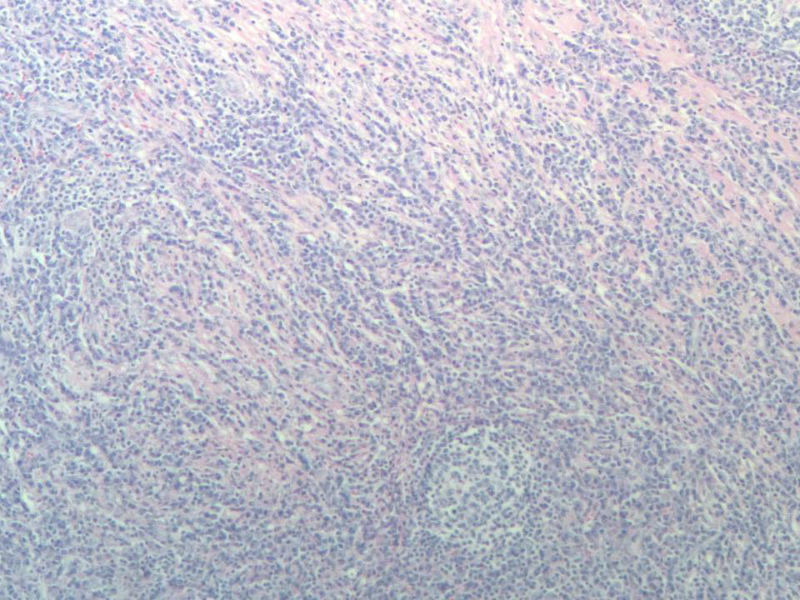

女,56岁,右颌下肿块两月余,检查肿块活动度差,手术切除。肉眼,灰白类圆形肿物,2X2X1厘米。包膜不完整,切面灰白色,质软。

与经治医生交流,患者目前一般状态良好,体表未触及肿块,CT各主要器官未见病变。结合免疫组化,我们考虑为浆细胞肉芽肿,但这个部位发生罕见,请指点!谢谢!

能产生显著淋巴滤泡的一些病变在很多专著甚至教科书中都有比较一致的描述。浆细胞肉芽肿的概念本身就有很多争议,WHO呼吸系统和软组织分册均将其归为炎性肌纤维母细胞瘤的同义词,似乎强调梭形细胞在其诊断中的意义。如果浆细胞肉芽肿是最合适的名称的话,那也是少见病例发生在少见部位并有不典型的形态学表现。

另外,网络读片不能完整地看到肿块的结构,肿块能否定是淋巴结吗?如果是淋巴结,我个人没有淋巴结浆细胞肉芽肿的读片经验,能不能考虑或排除一下浆细胞型的castleman或其它?